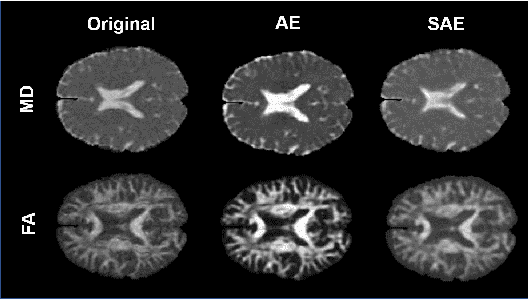

Abstract:Although neural networks have proven very successful in a number of medical image analysis applications, their use remains difficult when targeting subtle tasks such as the identification of barely visible brain lesions, especially given the lack of annotated datasets. Good candidate approaches are patch-based unsupervised pipelines which have both the advantage to increase the number of input data and to capture local and fine anomaly patterns distributed in the image, while potential inconveniences are the loss of global structural information. We illustrate this trade-off on Parkinson's disease (PD) anomaly detection comparing the performance of two anomaly detection models based on a spatial auto-encoder (AE) and an adaptation of a patch-fed siamese auto-encoder (SAE). On average, the SAE model performs better, showing that patches may indeed be advantageous.